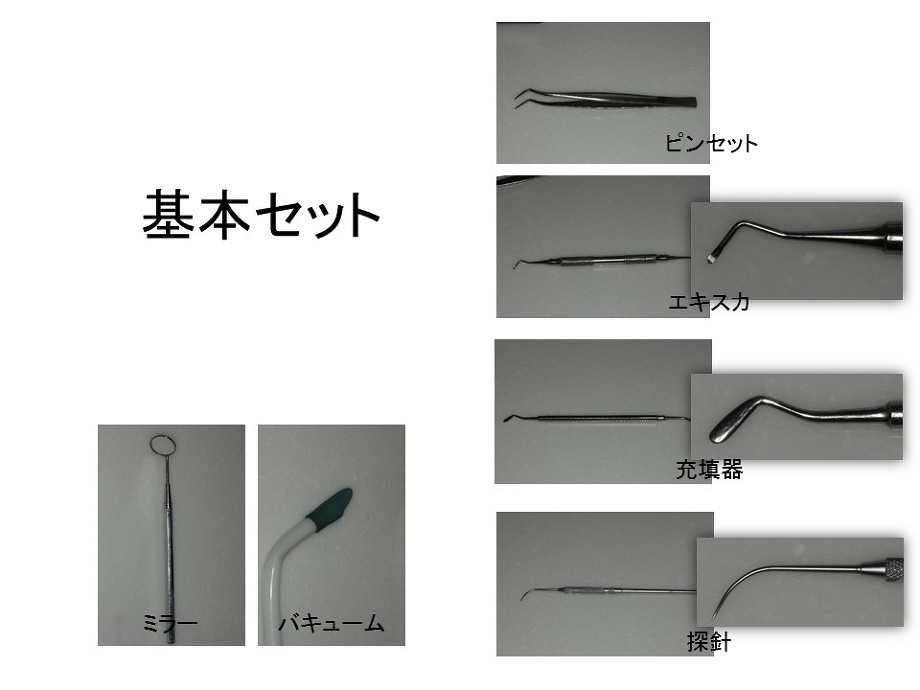

⑥ 前回詰めた綿花の状態を確認して、良い状態なら、「根管充填剤」(マスターポイント・アクセサリーポイント)というお薬を、余分な空間がないように根っこに詰めます。

⑥ 前回詰めた綿花の状態を確認して、良い状態なら、「根管充填剤」(マスターポイント・アクセサリーポイント)というお薬を、余分な空間がないように根っこに詰めます。 Q1.痛みはありますか?

Q1.痛みはありますか? ② 次に、「根管長測定器」という機械を使い、根っこの長さを正確に測ります。

② 次に、「根管長測定器」という機械を使い、根っこの長さを正確に測ります。

⑤ 次に、仮詰めをします。

⑤ 次に、仮詰めをします。 虫歯が神経まで達して炎症を起こしているので、人によってはズキズキとした痛みを感じる方もいます(>_<)